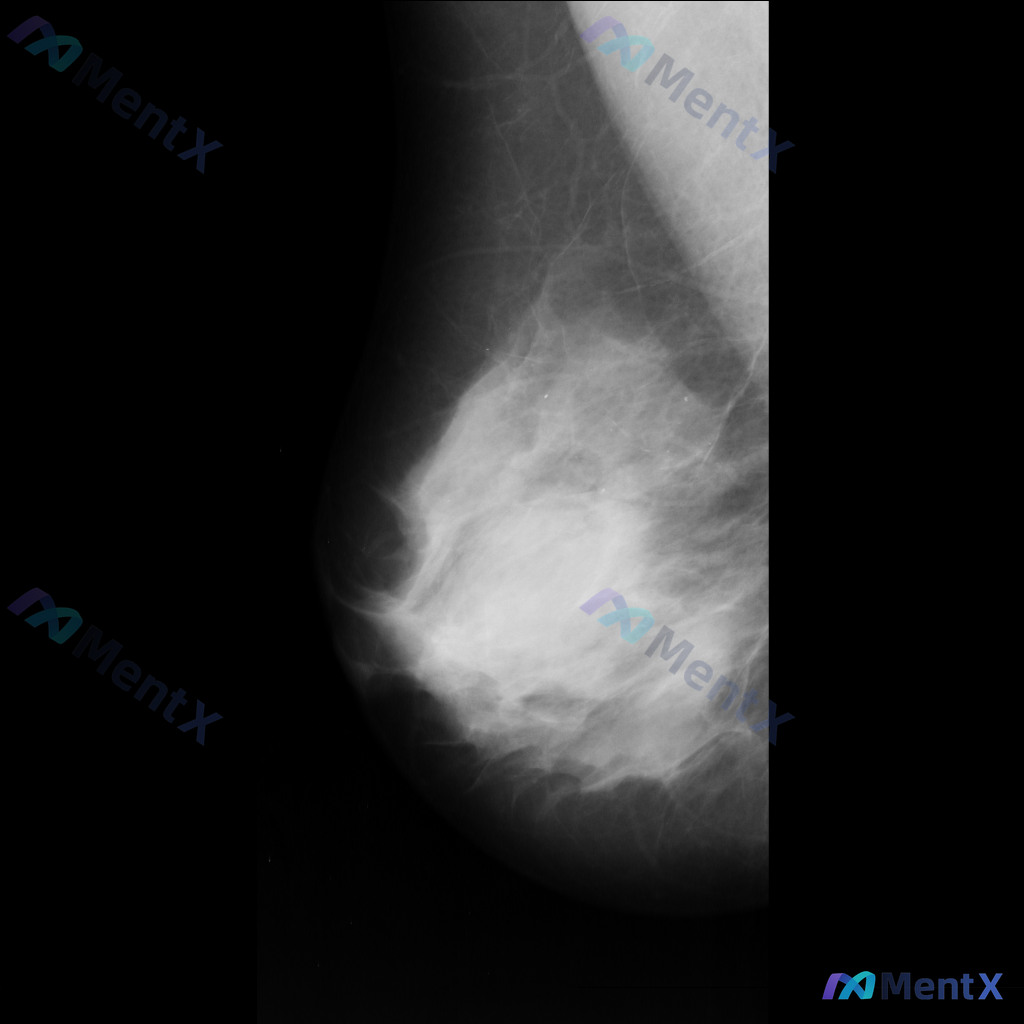

整理到一张乳腺钼靶影像的讨论资料,右乳可见一处病灶。 想先请大家看看:针对这张影像的异常表现,用什么术语描述最准确全面?另外结合征象,第一反应会往哪个方向考虑?

整理了一张乳腺钼靶影像的讨论资料,先和大家分享一下读片描述: 影像可见:不规则、高密度肿块/不对称致密影,伴有毛刺状边缘、结构扭曲和散在钙化。 目前考虑可能存在几种不同的异常方向,想先听听大家的第一反应——单看这组影像特征,你会先往哪种情况考虑? 也可以说说你最关注的是哪一点表现。